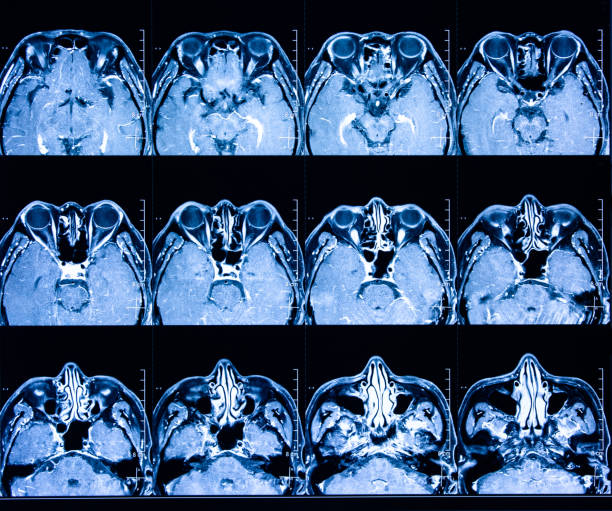

為了描述目的,患者按入組順序被賦予編號(hào),并被連續(xù)分配到三組中的一組,每組三名。根據(jù)模型2分割,ICH體積范圍為0.1至54.9mL(平均ICH體積為23.5mL)。5名ICH患者受累于局限性腦葉,其余患者受累于基底神經(jīng)節(jié)或外囊深處。3名患者的ICH位于丘腦(圖1),1名患者的血腫位于多個(gè)腦結(jié)構(gòu)(即尾狀核、殼核和蒼白球)。平均而言,MSCs是在ICH后3天注射的。